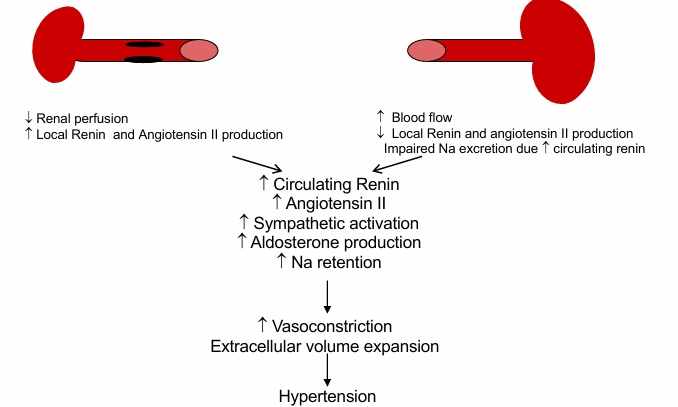

renovascular hypertension

pathogenesis of many acquired or genetic forms of secondary hypertension